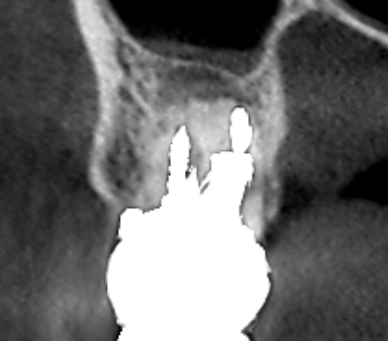

6カ月後の経過観察時の矢状断のCT画像です。矢印の先にあった膿の影が消え、歯槽骨が再生しています。

6カ月後の経過観察時の冠状断のCT画像です。矢印の先にあった膿の影が消え、歯槽骨が再生しています。